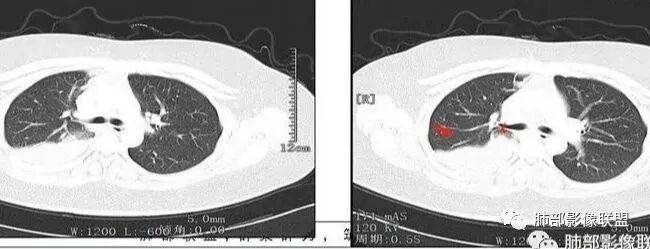

右肺体积缩小,右肺门可见片状影,叶支气管堵塞,呈低密度,无强化,其内似可见点状高密度钙化,病变外周膨隆,右肺下叶大片状致密影,增强后明显强化,其内血管走形自然,右肺下叶呈肺不张改变。纵隔肺门无肿大淋巴结。年轻女性,高热、黄痰来诊。综合考虑:右肺中、下叶综合征合并下叶肺不张,考虑炎性病变,炎性叶支气管阻塞可能性大,早期肺脓肿?结核有点不符合,无胸水,病灶形态太单一。

右肺中叶粘液栓,中叶低密度肿块,密度均匀,延迟强化,右肺下叶不张,考虑炎性病变

从CT看难度大。女,27岁,发热6天,咳嗽咳痰3天。无呼吸困难。右中间支气管堵塞?右下肺不张,大支气管堵塞常见原因:结核、肿瘤、异物。无呼吸困难,感觉病程较长,肺不张导致的肺功能下降有一定耐受。堵塞支气管似见低密度病灶,强化不明显,粘液表皮样癌?腺样囊性癌?鳞癌?还是结核?有待支气管镜进一步检查。

首先考虑支气管内肿瘤(如类癌、腺样囊性癌),导致阻塞性不涨

临床发热,腹泻,咳黄痰,应该是感染性病变。影像表现为下叶,中叶支气管堵塞,远端支气管内粘液潴留,所属肺组织不张,膈肌明显升高,上叶代偿性肺气肿,增强似乎可见中间段支气管处一个强化结节,考虑中间段支气管占位性病变合并远端支气管粘液潴留,感染可能,肿瘤性质不好定,太年轻,猜一个,粘液表皮样癌

年轻女性,发热6天,咳嗽咳痰三天

CT扫描示右肺下叶支气管堵塞,类圆形大肿块伴胸膜下大片肺实变影,增强扫描类圆形肿块延迟强化,见少量坏死,余实变区增强可见内部血管走行。纵隔见肿大淋巴结。考虑为恶性病变伴右肺下叶肺不张

患者青年女性,发热6 天,咳嗽、咳痰3天。为黄脓痰。胸部CT:右肺体积稍小,右中间支气管肿物堵塞,中叶、下叶大片实变不张,与正常肺组织分界清楚。增强实变影明显强化,右下肺支气管近心端见类圆形强化结节影,血管纤细,部分支气管显影变细,纵隔淋巴结肿大。结合无呼吸困难症状,病程长。综合考虑低度恶性病变并阻塞性肺炎,类癌可能大,鉴别结核、淋巴瘤。